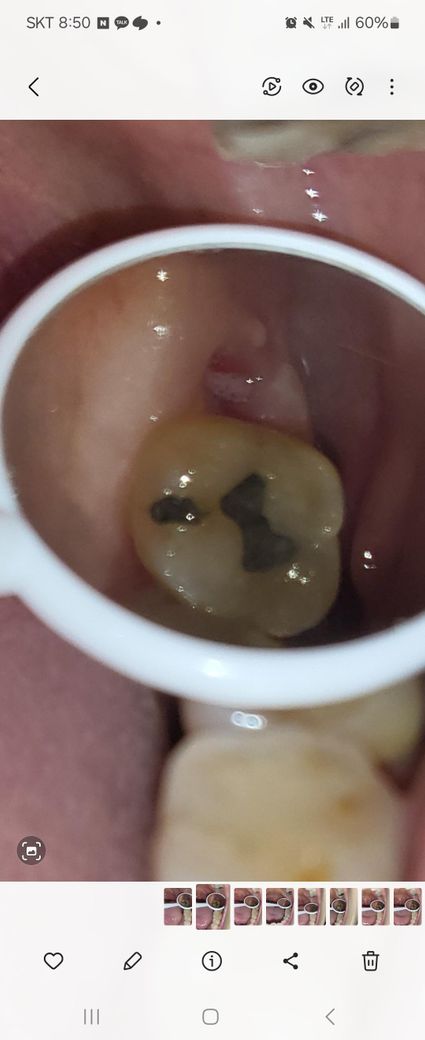

안녕하세요 상악사랑니 발치 16일차에요

사랑니발치11일차에도 이물감에 내원했는데 그땐 이상소견없었고 집에서 헥사메딘도 10일사용해서 중단상태인데 발치 12일차부터 잇몸에 하얀게 발치구멍이 아닌 잇몸 볼닿는 측면과 그윗부근 하얀돌기가 하나 올라와있어요.

냄새나 열 및 통증은없고 여전히 이물감느낌만 .. 전부터 계속 느껴졌음 . 모양이 매끄럽지않아지고 하얀게 점점 늘어난것같은 것같아서요. 이건 뭐일까요? 구내염일까요? 그냥자연회복 될까요?

전문의 선생님 사진한번 봐주세요ㅠ

• 1번 째 사진

사진상으로 보면 크게 문제가 잇는건 아니고 잇몸이 치유되면서 생기는 자연스러운 현상이니 너무 걱정하지 않으셔도 될것같습니다.

일단 사진상으로는 치유과정에서 생겼다 없어지는 단순 염증으로 보입니다. 해당 부위 위생관리 잘해주시면서 지켜보는 것도 좋을 것 같습니다.

사랑니 발치 후에는 하얀 막이 생기는 것이 정상적인 과정이며 그대로 지내셔도 괜찮습니다.